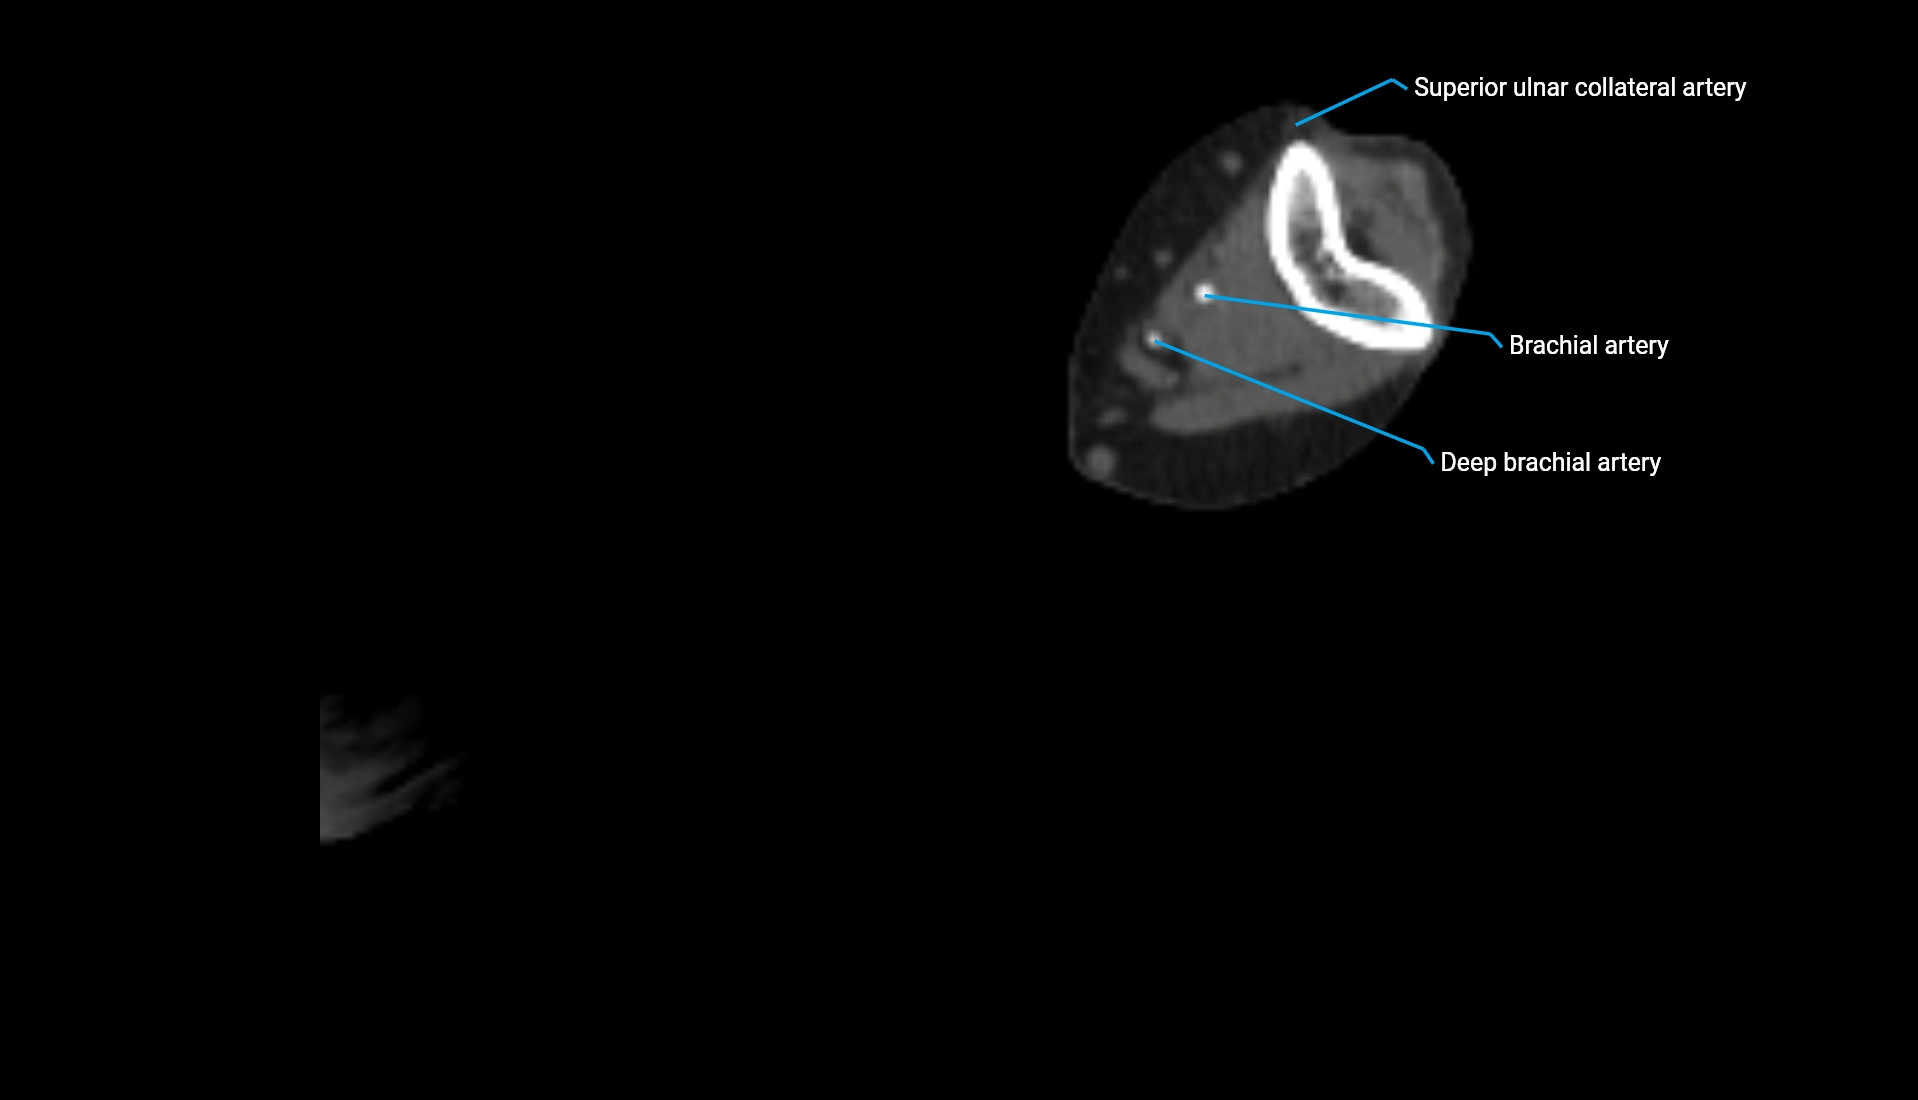

CT Appearance

Non-Contrast CT:

• Cortex: High-density, sharply defined

• Subchondral bone: Dense cancellous matrix

• Articular surface: Smooth concave contour articulating with the capitellum

• Excellent for evaluating bone integrity, alignment, and subtle fractures

Post-Contrast CT:

• Bone: No enhancement

• Joint capsule and synovium: Mild enhancement outlining the joint

• Improves contrast between soft tissues and bony margins

• Useful in detecting subtle joint abnormalities or postoperative changes